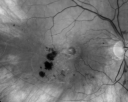

OD: Vertical C/D ratio is 0.2. There is an inferotemporal macular branch retinal vein occlusion. There is a well-defined, almost perfectly circular ring of pigment epithelial atrophy centrally, which is something you would see in someone who has had chronic severe cystoid macular edema for a long time.

OCT SCAN: The OCT scan shows in the right eye retinal atrophy. The left eye shows macular edema. Photos confirm clinical findings.

FLUORESCEIN ANGIOGRAPHY: Fluorescein angiography confirms a branch retinal vein occlusion in both eyes with severe capillary non profusion of the inferior half of the macula in the right eye and the superior half of the macula in the left eye. There is late leakage into the fovea in the left eye.

New BRVO Left Eye Old BRVO Right Eye - Right Eye Showing Bulls Eye Atrophy from Chronic CME and Non-Perfusion Infero-temporally575 views90-year-old man decreased vision maybe one year since cataract surgery he is no longer able to read. OD 20/200, OS 20/200     (0 votes)